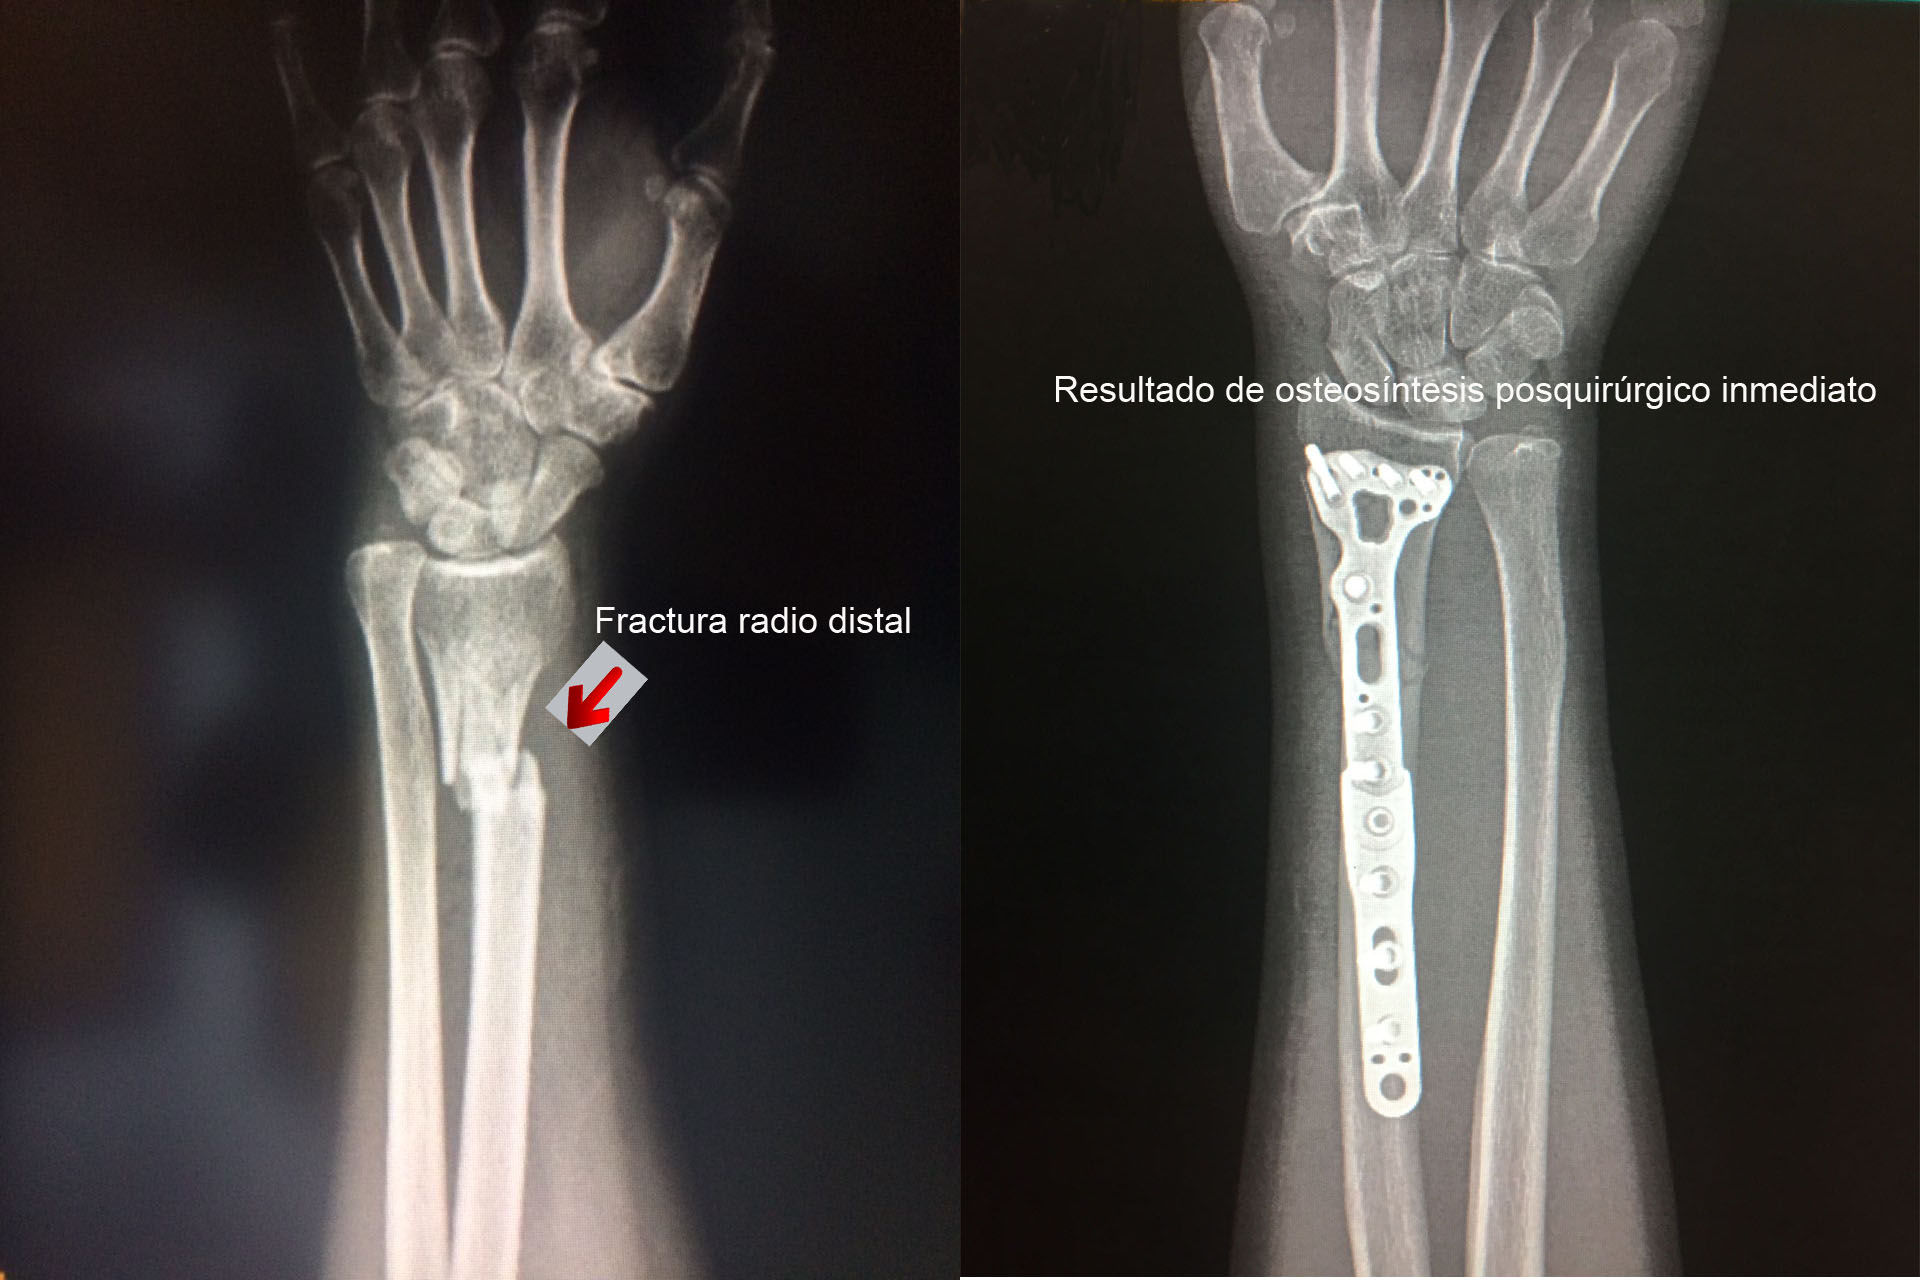

Una fractura ósea es la ruptura de un hueso, la cual puede presentarse por diversas causas y su tratamiento dependerá de la magnitud, sitio anatómico y de las enfermedades concomitantes. Algunas pueden manejarse de forma conservadora con solo inmovilización y hay otras que requieren de un tratamiento quirúrgico. A continuación, podrá ver algunos casos quirúrgicos, dando clic a la zona del cuerpo afectada.